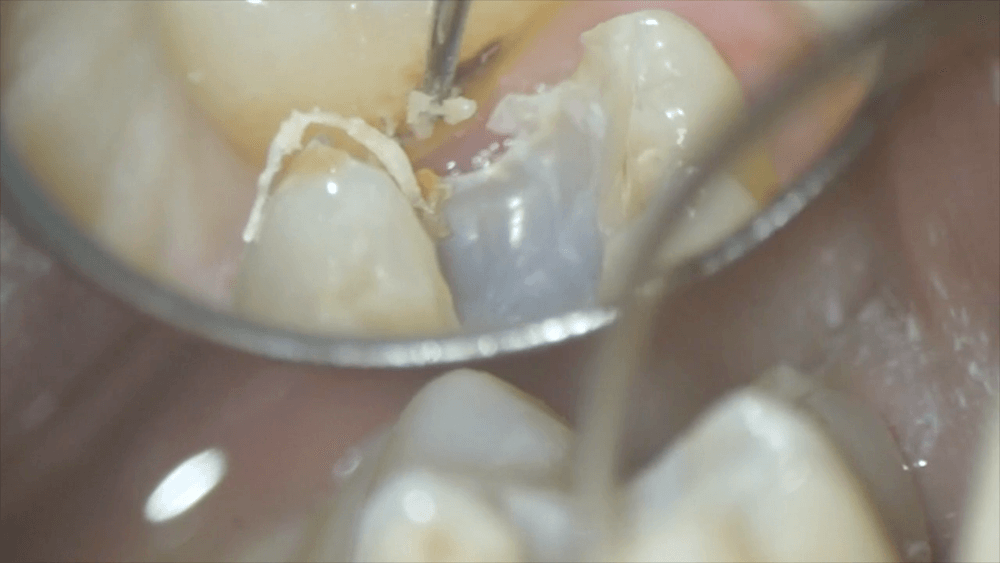

取り除くと、となりの歯の側面が見えました。黒くなっています。これは虫歯になりかかっている状態です。

この部分を触ると、虫歯の原因であるプラークがたくさん出てきました。

この手前の歯が虫歯になりかかってるのは、精度の悪いつめ物のせいで溜まったプラークが影響している可能性が高いです。精度の悪いつめ物は、となりの歯にまで影響してしまうのですね。